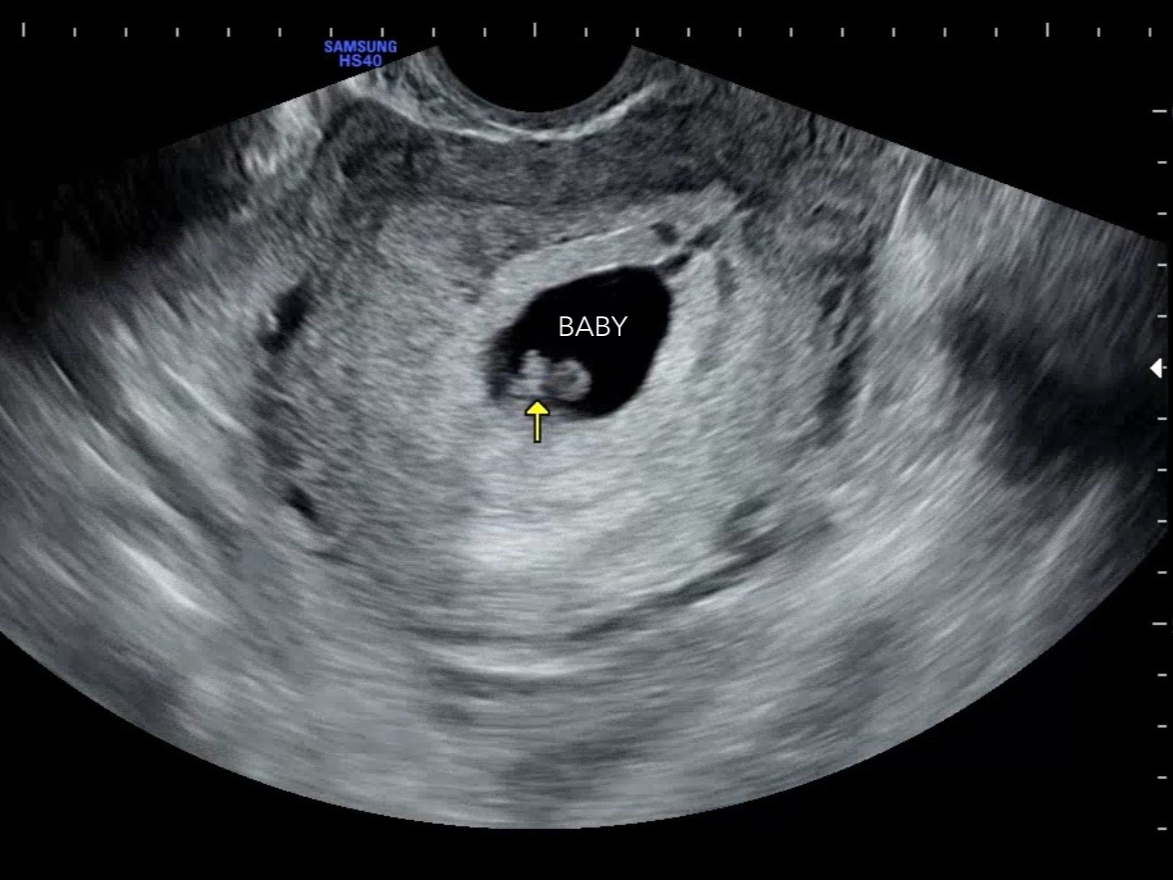

5주에서 6주쯤에는 초음파에서

아기집이 보이기 시작하고,

7~8주에는 심장소리도 들을 수 있어요.

저는 6주 차에 방문해서 반짝반짝 심장 깜빡임을 확인했고

7주 차에 다시 방문해서 심장소리를 들었어요.

6주 차 진료에서 아기집을 확인했고

7주 차에는 태아 심음을 듣고 산전검사를 받았어요.

본격적으로 아기의 존재를

눈으로 확인할 수 있는 시기예요.